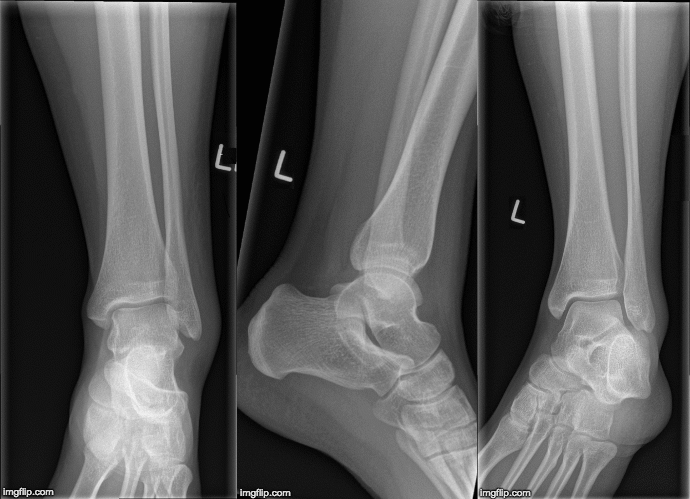

Simptomi Svaki zglob može biti zahvaćen sarkoidozom, ali glavni zahvaćeni zglobovi su stopala, gležnjevi i koljena.

Bolovi u zglobovima dijagnosticiraju se nakon savjetovanja s liječnikom. Povremeno su potrebna daljnja ispitivanja. To može uključivati rendgenske snimke vaših zglobova ili druge slikovne pretrage (ultrazvuk ili MRI). Vaš liječnik može uzeti uzorak tekućine iz vašeg otečenog zgloba pomoću igle i šprice (biopsija).

Neki pacijenti mogu razviti iznenadnu bol i oticanje zglobova, najčešće na gležnjevima. U isto vrijeme mogu razviti bolne crvene ili ljubičaste kvrge na potkoljenicama. Ove promjene na koži nazivaju se 'nodozni eritem'. Kada se ovi simptomi pojave zajedno, vaš liječnik može dogovoriti rendgensko snimanje prsnog koša kako bi se potražile povećane limfne žlijezde u prsnom košu.